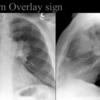

Hilum  overlay sign

Mass in front or behind hilum

see next image